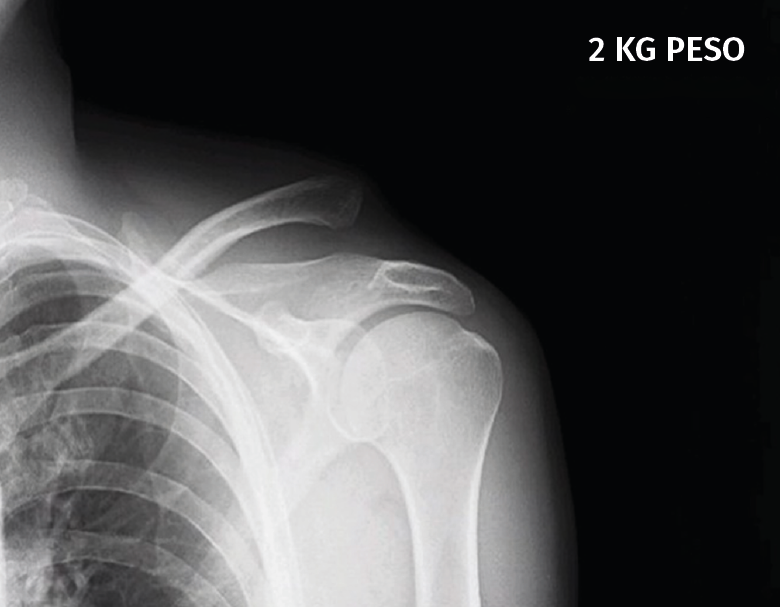

Figura 1. Caso demostrativo de la luxación con la sujeción por parte del paciente de 2 kg de peso.

La exploración clínica se realizó mediante la valoración del denominado signo de la “tecla” (desplazamiento vertical) y del desplazamiento horizontal. Se completó el diagnóstico mediante radiografía simple anteroposterior (AP) comparativa de ambos hombros. En los casos de duda en relación con el grado de la lesión, esta proyección se realizó con la sujeción por parte del paciente de 2 kg de peso (Figura 1). No se creyó necesaria la realización sistemática de tomografía axial computarizada (TAC) ya que la exploración y la exploración bajo anestesia permiten establecer las direcciones y la importancia del desplazamiento. Tampoco se realizó resonancia, dado que la artroscopia permitiría, como así se demostró, diagnosticar posibles lesiones asociadas.